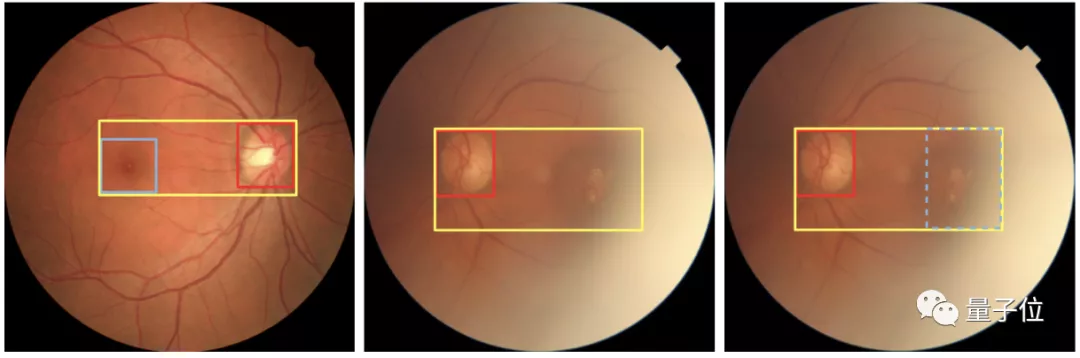

其中就包括医学图像处理领域顶会MICCAI上,一篇与莫纳什大学(药学专业全球TOP 2)合作的论文Retinal Abnormalities Recognition Using Regional Multitask Learning

论文中的AI视网膜影像识别模型,利用多任务学习语义分类,让三个子网络分别学习视网膜不同区域的疾病,最终实现自动精准识别36种视网膜病变。